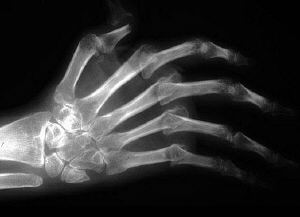

2. The following can be associated with the pictures above:

a.

b.

c.

d.

e.